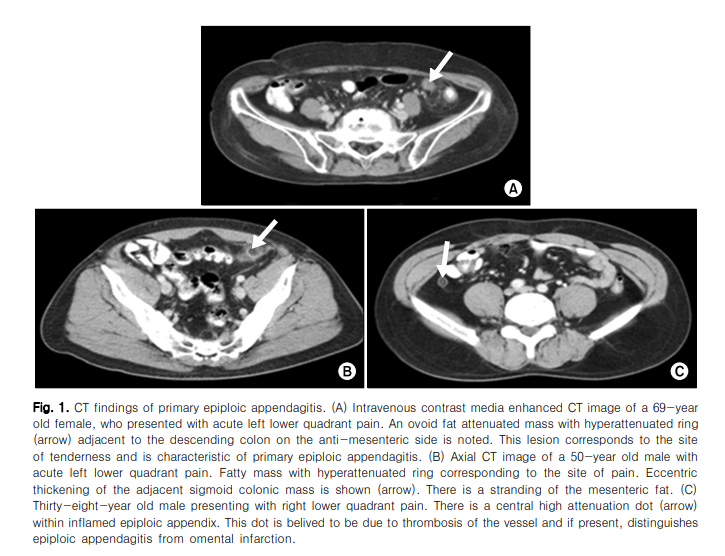

복부 전산화 단층촬영에서, 정상적인 복막수는 복 강내에서 관찰이 되지 않으며, 염증이 있는 경우, 복막 수는 장주위에 난원형의 지방종괴로 보이거나, 경계 가 명확하고 고음영의 고리가 주변으로 보이거나, 종 괴 중심부에 고음영의 점이 관찰된다. 10 그밖에 복막 이 두꺼워지거나 주변 장의 압박 및 부종이 관찰되기 도 한다. 10 이러한 특징적인 전산화 단층촬영 소견이 있음에도 불구하고, 진단을 위해서는 감별진단 질환 들인 급성 충수염과 게실염을 먼저 배제하는 것이 중요하다.